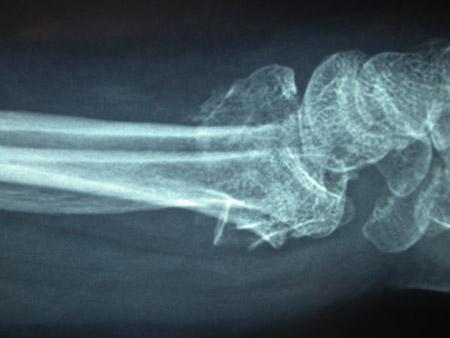

Uma avaliação radiográfica inicial é necessária para se ter um diagnóstico conclusivo de fratura do rádio distal.[30] Geralmente, são feitas radiografias em incidência posteroanterior, lateral e carpal.[30]

As fraturas podem ser fissuras mínimas, fraturas extra-articulares ou fraturas intra-articulares.

A radiografia também pode indicar o grau de osteopenia e dar alguma informação sobre o grau de comprometimento articular ou cominuição.

Embora incomuns, lesões combinadas do rádio distal e do escafoide são observadas. As radiografias também devem ser examinadas em relação à fratura do escafoide.[2][Figure caption and citation for the preceding image starts]: Fratura extra-articular do tipo A do rádio distal: vista lateralDo acervo do Dr. Chaitanya S. Mudgal [Citation ends].